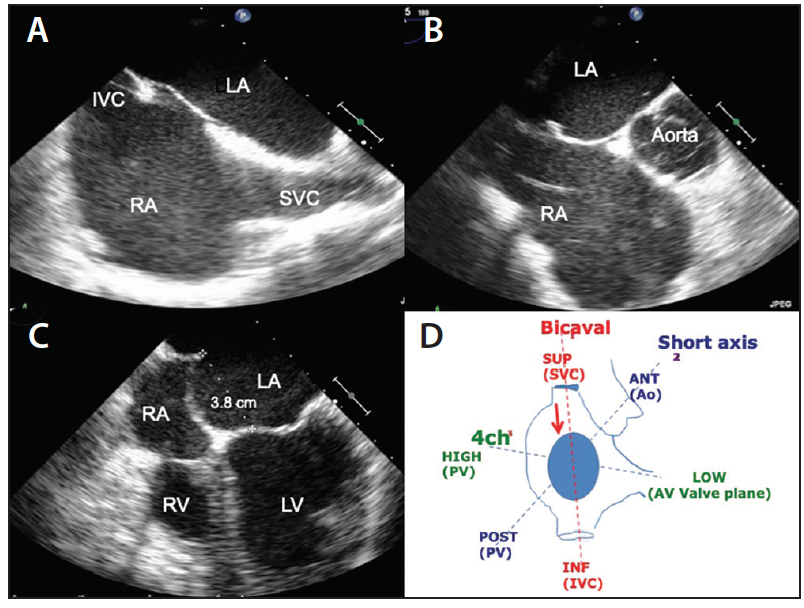

Next, under TEE monitoring (bicaval view), the needle and sheath are pulled back until they fall into the fossa and tenting is obtained (Figure 5A). At this point, TEE moves to the short axis (SAX) at the base view and position of the tenting is checked; it should be posterior in most patients undergoing mitral interventions (Figure 5B).

Figure 5. TEE bicaval view (A), SAX at the base view (B), and four-chamber view (C) during the pullback phase of TP. Schematic view of the three main TEE projections used during TP in relation to the anatomic structures they show (D). 4ch, four chamber; ANT, anterior; Ao, aorta; AV valve, atrioventricular valve; INF, inferior; IVC, inferior vena cava; LV, left ventricle; PV, pulmonary vein; RV, right ventricle; SUP, superior.

Once the transseptal system falls into position in the fossa, to change positions, the operator has to move in two directions at the same time to prevent pivoting of the needle. An isolated clockwise rotation will result in rotation of the sheath without a change in the contact point. To move posteriorly, the operator has to combine rotations with slight pulling of the catheter to allow mobilization of the tip—if the tenting is too anterior, a clockwise torque on the needle with an associated slight pullback movement is done under fluoroscopic guidance to move posteriorly; if the tenting is too posterior, a counterclockwise rotation with concomitant pullback movement should be applied.

In the case of MitraClip (Abbott Vascular) procedures, TEE should now switch to the four-chamber view and measure the height of the puncture (the distance between the tenting and the mitral annulus) (Figure 5C). In patients with degenerative mitral regurgitation, the ideal height is > 4 cm, whereas in functional mitral regurgitation, a 3-cm distance is acceptable. Given the flexibility of the membranous septum, the height of the puncture may be reduced during steering of the devices; therefore, in the presence of a floppy septum, higher punctures may be recommended.

Ideal locations of the puncture depend on the specific devices used and the patient characteristics. A MitraClip procedure is usually performed with posterior punctures in the segments superior-posterior and inferior-posterior. A Cardioband (Edwards Lifesciences) procedure is performed with more anterior punctures (superior-anterior and inferior-anterior) and left atrial appendage closure is usually performed through an inferior puncture (usually inferior-posterior). Main TEE projections and related visible anatomic structures are shown in Figure 5D.